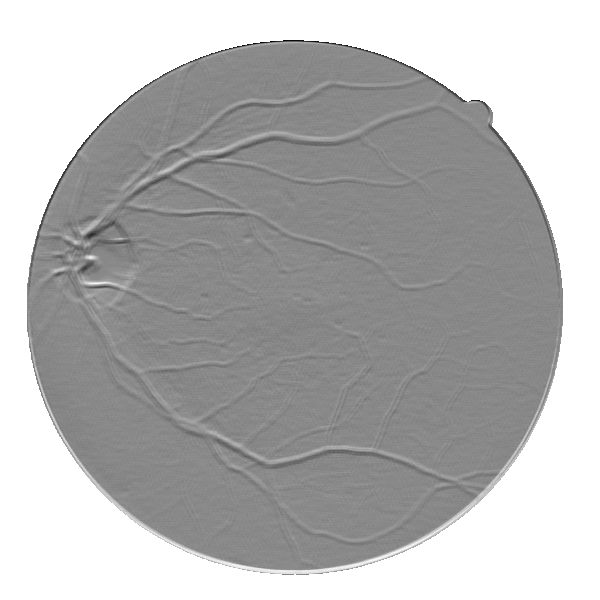

Except for the STARE database, in both the remaining databases there is no clear difference between the marking pattern of the experts. That is, we can see cases where the first observer marks vessels that the second one does not see and vice versa. This may be deduced from Fig. 7, where we compare the annotations of both observers, for each database. We believe that this noticeable discordance may become a limiting factor for future improvements since the current results of this field are already extremely accurate.